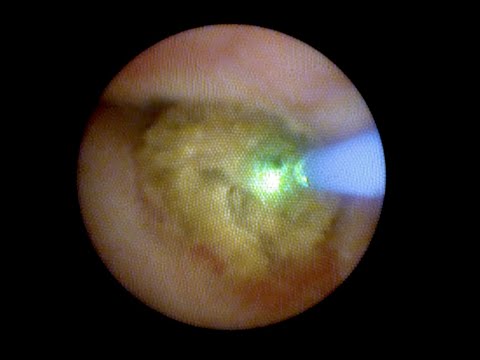

#ureteroscopy for 1 cm ureteral stone

w/ #RevoLixHTL #TmYAG #laser

🔹10 Watts - 10 Hz - 100% effect

🔹Wolf Miniureteroscope

https://youtu.be/7Hd4X5RIHZU via @YouTube